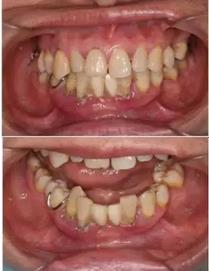

初診時(shí)下前牙不良修復(fù)體

導(dǎo)板就位后逐級擴(kuò)孔

臨時(shí)冠就位,即刻修復(fù),無咬合接觸